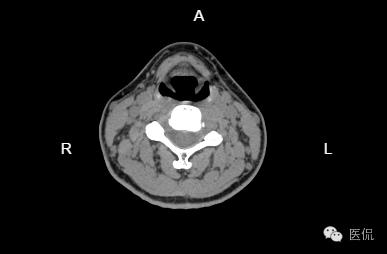

患者信息:女,35岁

检查部位:颈椎

检查方法:C2-6间盘平扫

患者主诉:间断性头疼、头晕恶心一个月左右,右侧上肢手臂麻木,暂无其他不适症状。

颈椎曲度变直,序列稳定,诸椎体密度未见异常,CC3-4椎间盘轻度向后突出,局部硬膜囊受压,C4-5、C5-6椎间盘未见明显膨出、突出,椎管无狭窄。椎管内未见异常密度。椎旁软组织未见异常密度影。

诊断意见:

1. 颈椎曲度变直。

2. C3-4椎间盘突出。